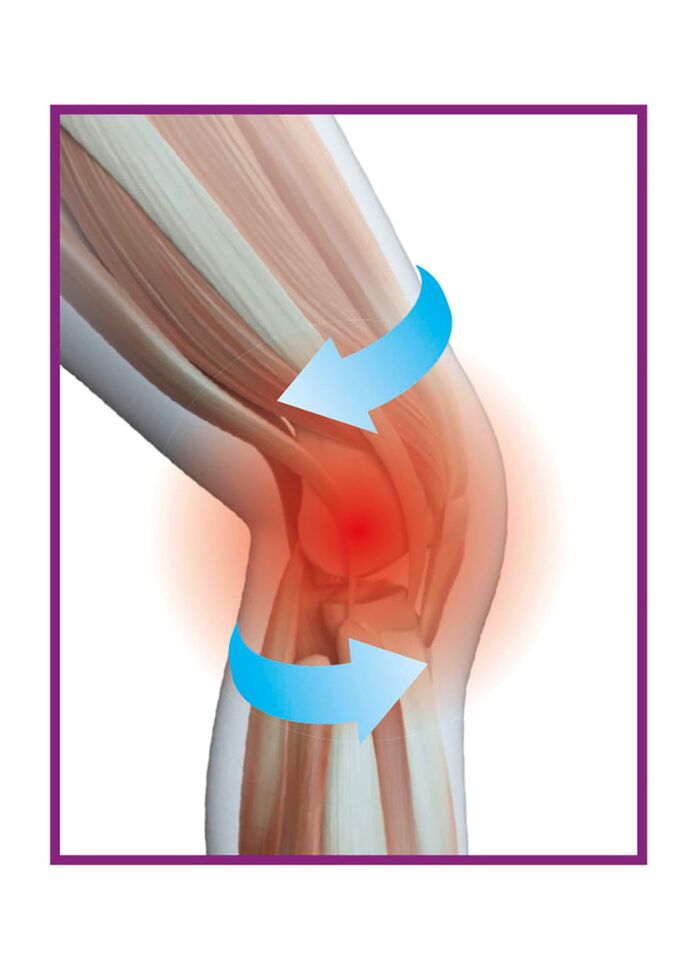

Vitalmaxx Bandagen mit Kupferfasern